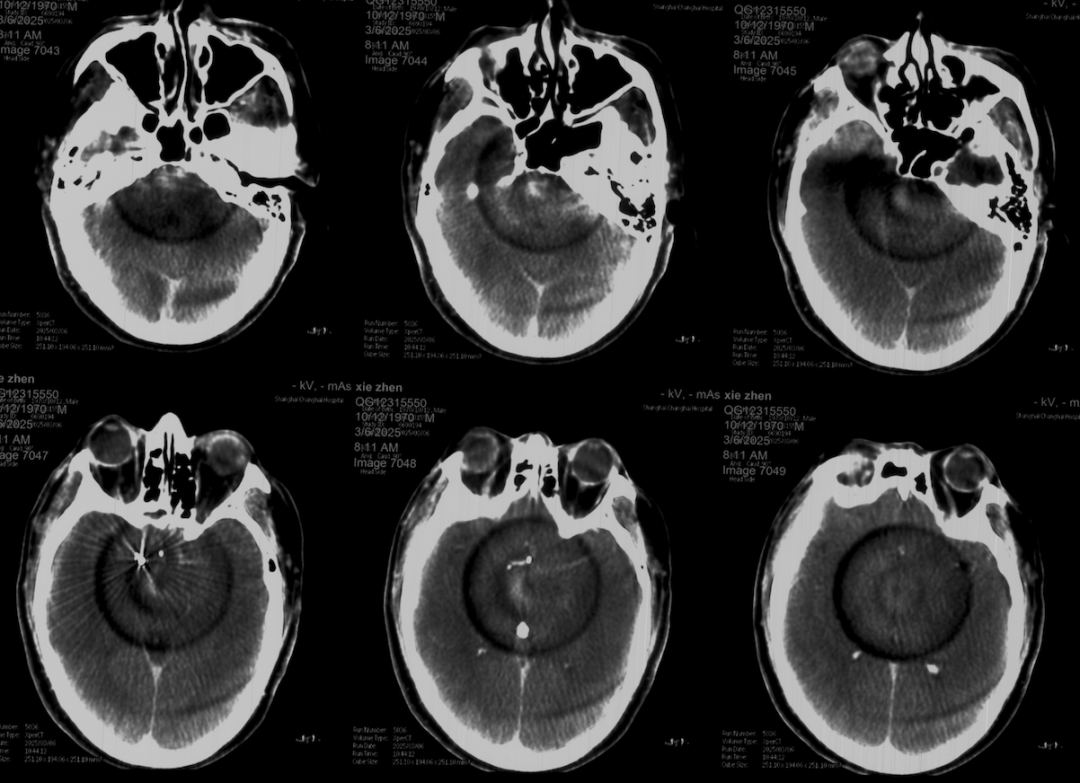

术前外院 DSA 2025-02

箭头所指右侧A1微小动脉瘤

工作位正位造影(图片)

工作位侧位造影(图片)

工作位正位造影(视频)

工作位侧位造影(视频)